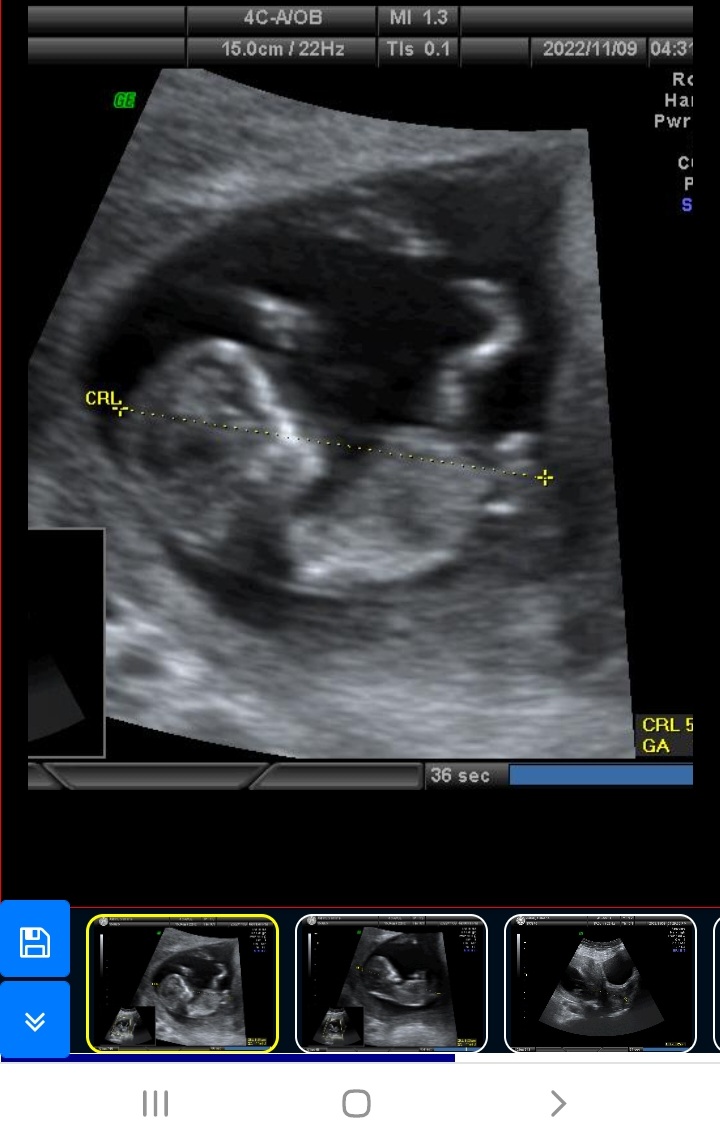

جدی؟ یه سوال همه بچه ها توی ۱۳ هفته این شکلین؟ یا فقط بچه من اینطور خیلی ناراحتم فکر میکنم بینی و پی ...

😂😂ن فقط جمجه پسر اینجوری تو این هفته ها بعد مثل هم میشن واسه دختر پیشونیش صافه منم رفته بودم میگفتم وای چ دماغی داره بچم بعد ک دنیا اومد دماغش اندازه نخود😁